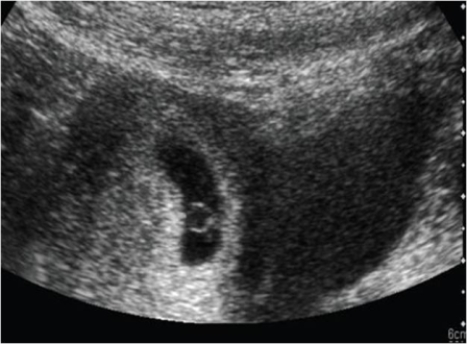

Male and Female Urinary Tract and Male Genital Tract